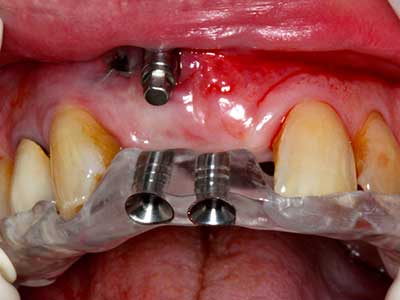

Fig. 13: Adequate irrigation with the 4-mm residual bone width is essential for this 52-year-old patient during the bone splitting.

Fig. 14: Placement of four tapered RSX implants (Bego Implant Systems, Bremen).